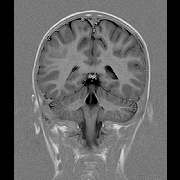

脳ドックについて

脳卒中をはじめとする脳の病気は、急に症状が現れることがあります。

脳ドックは、自覚症状のない脳動脈瘤(クモ膜下出血の原因)、脳腫瘍等の早期発見を目的に検査を行います。